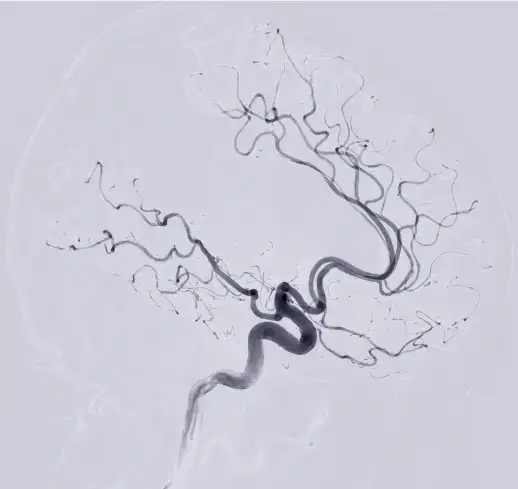

뇌경색 원인 2. 뇌동맥류

뇌동맥류는 뇌혈관이 약해져 부풀어 오른 것을 말합니다. 뇌동맥류가 터지면 뇌출혈이 발생할 수 있습니다.